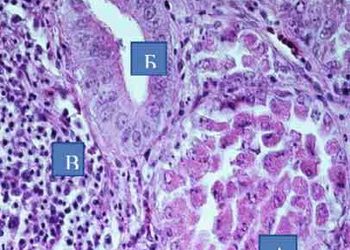

А ‒ некроз, десквамація секреторних клітин альвеод;Б ‒ заміщення втрачених залозистих клітин альвеоли протоковим циліндричним епітелієм; В ‒ лімфоїдна...